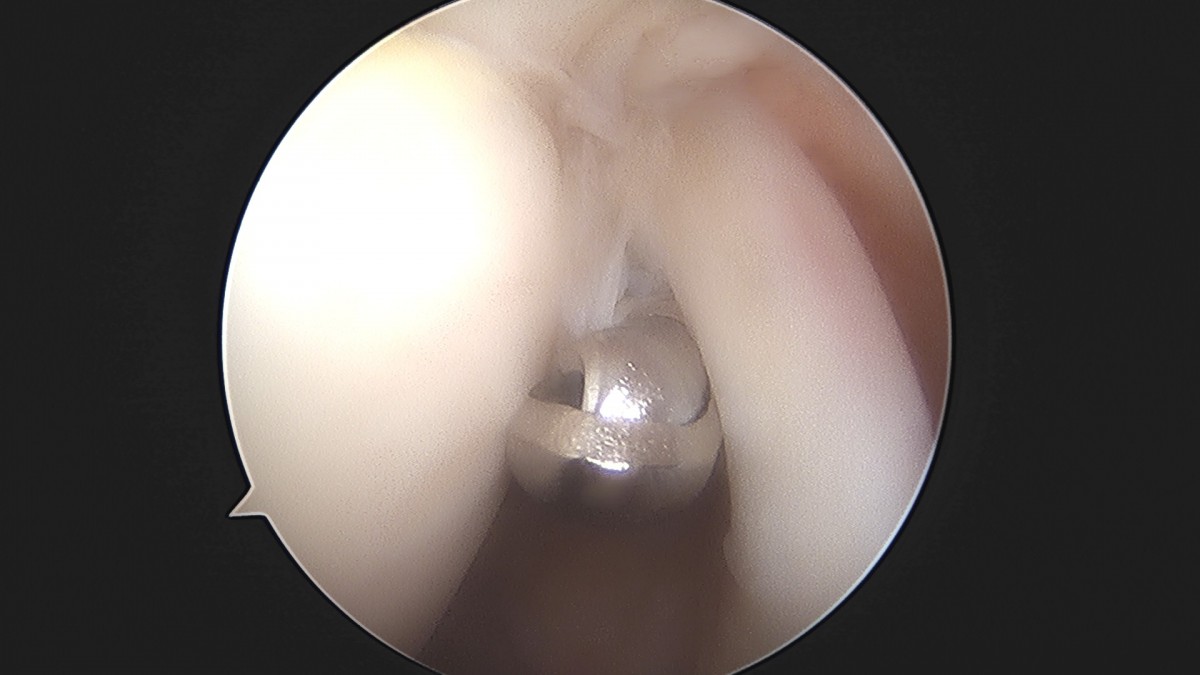

이재상원장님 어깨 견봉하 감압술 및 관절낭 이완술 주혜O 환자

dae765e4d9ac96aee867c9d6292d8784_1758003914_0014.jpg